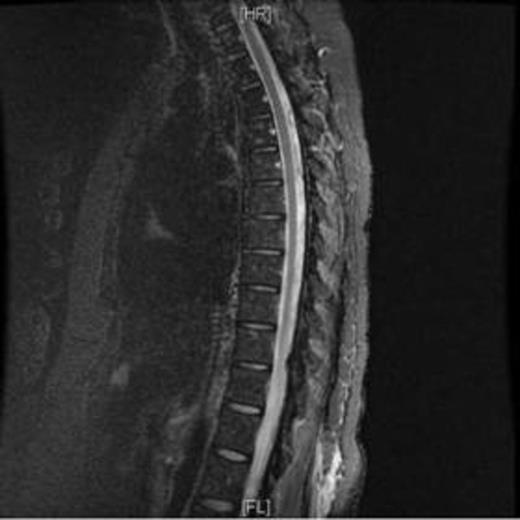

A sixty-one year-old Hispanic female with Waldenstrom’s Macroglobulinemia diagnosed in 2011 and successfully treated with 6 monthly cycles of Cyclophosphamide, Rituximab and Dexamethasone (CDR) from 12/11 through 5/12 was then put on a two-year maintenance scheme with Rituximab every three months. In February, 2014 (six months before the end of the planned treatment), she came to the ER complaining with severe headache, aphasia and blurred vision. A stroke was initially ruled out and she received Paracetamol with partial improvement. Nonetheless, symptoms re-appeared accompanied with disorientation and agitation. Antipsychotic medication was given with no improvement. On PE she was disoriented with aphasia, paraparetic and neck stiffness suggestive of meningitis. Blood tests, a MRI and lumbar puncture were performed showing leptomeningeal hyperintensity with no signs of encephalitis (Figure 1).